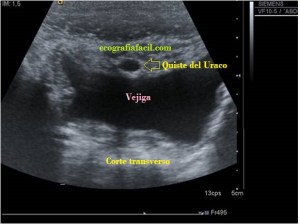

Bien, hemos visto una lesión que es un quiste hidatídico calcificado, pero te preguntarás, si nunca viste uno, ¿cómo es uno cuando tiene «hijas»?, es decir, cuando está activo…Mira este corte transversal de un hígado:

La LOE es de aspecto redondeado, heterogéneo, con multitud de pequeñas imágenes anecoicas e hipoecogénicas, de diferentes tamaños. Esta lesión fue estudiada también mediante otra técnica de imagen, la RMN donde se observa una imagen hiperdensa, con una amalgama de lesiones bordeando a periferia de la misma, de distintos tamaños como se objetiva en la imagen del mismo paciente, de la ecografía inmediatamente superior (Imagen 7). La lesión es activa, por tanto debió de ser tratada, la patología es potencialmente mortal en caso de que el quiste se rompiese.